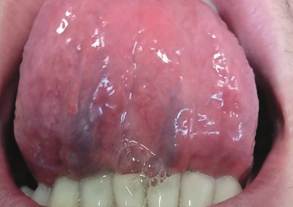

En la zona motivo de consulta, se aprecia en cara ventral de lengua dos placas blanquecinas, una de mayor magnitud en parte media de lengua, y otra de menor extensión en la mitad izquierda de la misma, ambas indoloras (figura 2). Se pregunta al paciente si presenta al momento alguna otra lesión en el cuerpo, lo cual niega. El diagnóstico presuntivo fue de sífilis secundaria, por lo que se solicitó crasis sanguínea y estudios serológicos complementarios de diagnóstico: reacción plasmática rápida (RPR) mide los anticuerpos (AC) liberados por las células huésped dañadas así como también por los treponemas. Dichos AC no sólo se producen como consecuencia de la sífilis sino también en respuesta a enfermedades no treponémicas de naturaleza aguda y crónica donde hay daño tisular. Por dicho motivo se realiza una segunda prueba más específica para detectar AC contra el treponema que causa la sífilis una de ellas es AC anti Treponema pallidum. utilizando el método de la quimioluminiscencia. También hepatitis B, C y VIH a fin de ampliar el protocolo de infecciones de transmisión sexual. El RPR arrojó un valor de 1024 unidades siendo el resultado óptimo: 0–0,001 y la quimioluminiscencia de 28.10 considerando que a partir de 1.0 ya es positiva, mientras que las demás pruebas serológicas resultaron no reactivas (figura 3).

Figura 2. Lesión en cara ventral de lengua.

Confirmado el diagnóstico de sífilis secundaria, se realizó la correspondiente derivación del paciente al centro de salud para recibir el tratamiento adecuado, donde fue medicado con tres dosis de penicilina G benzatínica 2.400.000 UI intramuscular. Post tratamiento se controló al paciente observando una notable mejoría de la lesión, evolucionando a la remisión de la misma (figuras 4A y 4B).

Figura 4A. Control luego de iniciado el tratamiento observándose una reducción de la lesión.

Figura 4B. Control luego de iniciado el tratamiento observándose una reducción de la lesión.